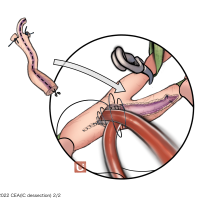

OPExPARK20220412コンテンツシリーズ

OPExPARK20220405コンテンツシリーズ

OPExPARK20220130コンテンツシリーズ

OPExPARK20220518コンテンツシリーズ

OPExPARK20220323コンテンツシリーズ

OPExPARK 2021013コンテンツシリーズ

OPExPARK 0915コンテンツシリーズ